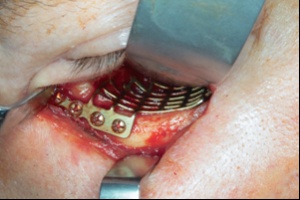

Signifikante Unterschiede wurden bezüglich des ISS nachgewiesen. Dieser lag bei den Schussverletzten im Mittel bei 23, bei den Explosionsverletzten bei 29 (siehe Abbildung 2). Auf das Gesamtkollektiv bezogen wurden im Mittel 33 % der Patienten im Rahmen einer Damage Control Surgery (DCS) erstversorgt (26 % der Schuss- und 41 % der Explosionsverletzten). Schussverletzungen hatten trotz -niedrigerem ISS keine geringere Anzahl an Operationen pro Patient.

Die praktischen Erfahrungen von Einsatzchirurgen der Bundeswehr im Management penetrierender abdomineller und/oder thorakaler Traumata, wie mit dieser Arbeit durch die Analyse der Behandlungsdaten im Einsatz belegt, zeigen, dass Patienten ohne ballistischen Schutz des Torsos vor allem bei thorakoabdominellen Verletzungen eine hohe Mortalität aufweisen und Explosionsverletzungen häufiger zur DCS-Indikation führen können. Es wird auch belegt, dass die Versorgung von Schuss- und Explosionsverletzten die Kenntnis und Kompetenz zur Durchführung von Damage Control Prozeduren des Thorax und des Abdomens voraussetzt. Es gilt, diese insbesondere bei den Einsatzchirurgen vorhandene Expertise und Erfahrung nun an die zivilen Kollegen weiter zu geben.